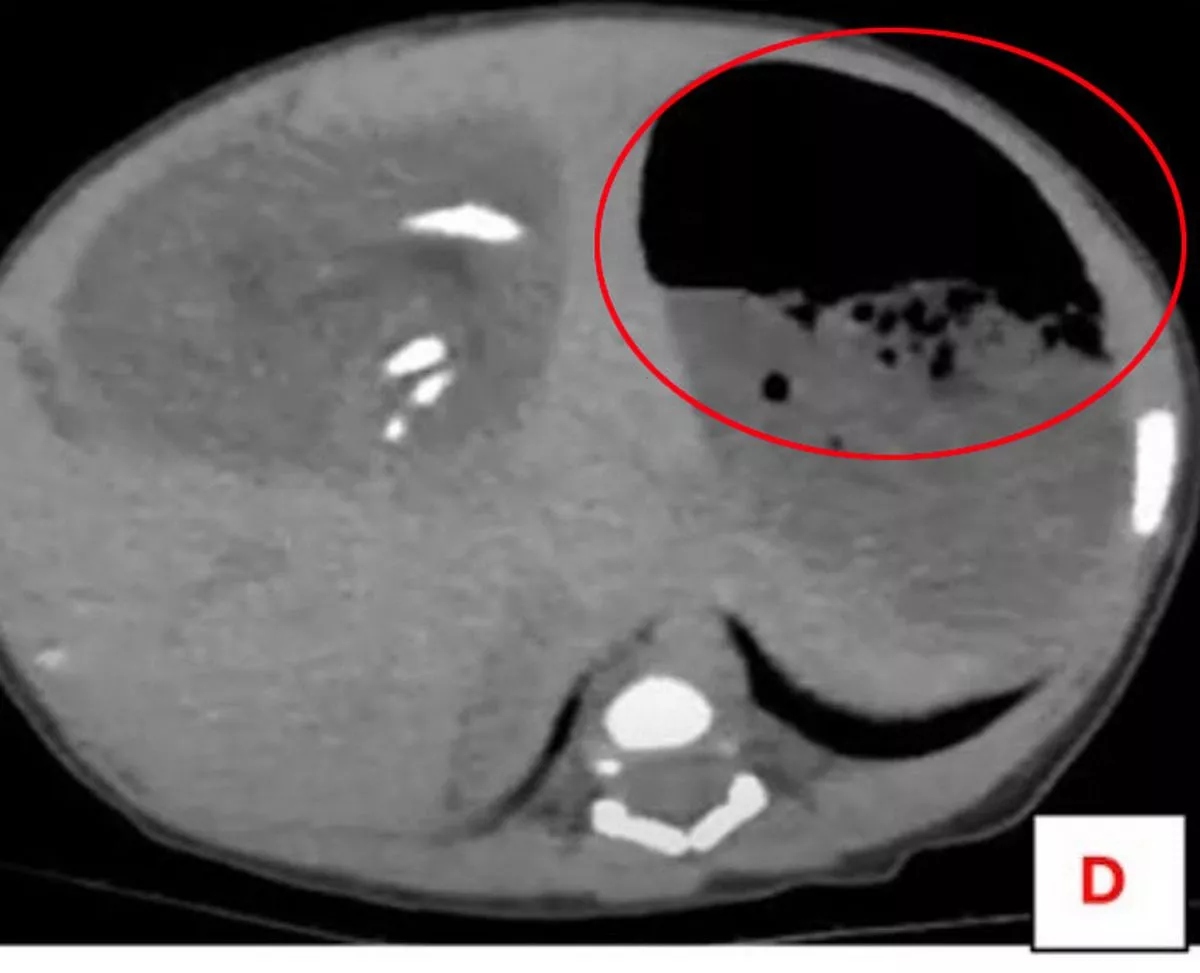

Chụp cắt lớp vi tính có cản quang ở dạ dày và xương chậu một lần nữa làm nổi bật khối u, lần này cho thấy các bộ phận xương bị biến dạng giống như xương dài, xương sườn, đốt sống, xương chậu và mô mềm.

Các bác sĩ có thể thấy thai nhi được nuôi dưỡng bởi một động mạch lớn và họ xác nhận phát hiện này là trường hợp thai trong thai – một dị tật cực kỳ hiếm gặp xảy ra khi một thai đôi ký sinh dị dạng phát triển bên trong cơ thể của anh chị em.

Theo NeedToKnow, các bác sĩ phẫu thuật đã thực hiện một ca mở bụng – rạch một đường vào khoang bụng và tìm thấy khối u gần gan.